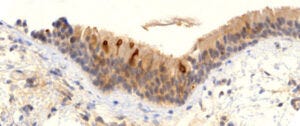

3. Expression of viral proteins can be detected with immunohistochemistry

While the distribution of the model vaccine leads us to expect widespread expression of the spike protein, we are here after solid proof. Such proof can be obtained using immunohistochemistry, which method is illustrated in this slide for the vaccine-encoded spike protein.

If a vaccine particle—composed of the spike-encoding mRNA, coated with lipids—enters a body cell, this will cause the spike protein to be synthesized within the cell and then taken to the cell surface. There, it can be recognized by a spike-specific antibody. After washing the tissue specimen to remove unbound antibody molecules, the bound ones can be detected with a secondary antibody that is coupled with some enzyme, often horseradish peroxidase. After another washing step, the specimen is incubated with a water-soluble precursor dye that is converted by the enzyme to an insoluble brown pigment. Each enzyme molecule can rapidly convert a large number of dye molecules, which greatly amplifies the signal.

At the top right of the image, you can see two cells which were exposed to the Pfizer vaccine and then subjected to the protocol outlined above. The intense brown stain indicates that the cells were indeed producing the spike protein.

In short, wherever the brown pigment is deposited, the original antigen—in this example, the spike protein—must have been present. Immunohistochemistry is widely used not only in clinical pathology but also in research; it could readily have been used to detect widespread expression of spike protein in animal trials during preclinical development. However, it appears that the FDA and other regulators never received or demanded such experimental data [6].

13. Vaccine-induced expression of spike protein in a bronchial biopsy nine months after vaccination

The slide shows a sample of bronchial mucous membrane, from a patient who is alive but has suffered respiratory symptoms ever since being vaccinated. We see several cells in the uppermost cell layer that strongly express spike protein—and this even nine months after his most recent vaccine injection! While this is indeed the most extreme case of long-lasting expression, there is evidence both from Burkhardt’s autopsies and from published studies on blood samples [7] or lymph node biopsies [8] to indicate that expression does last several months.